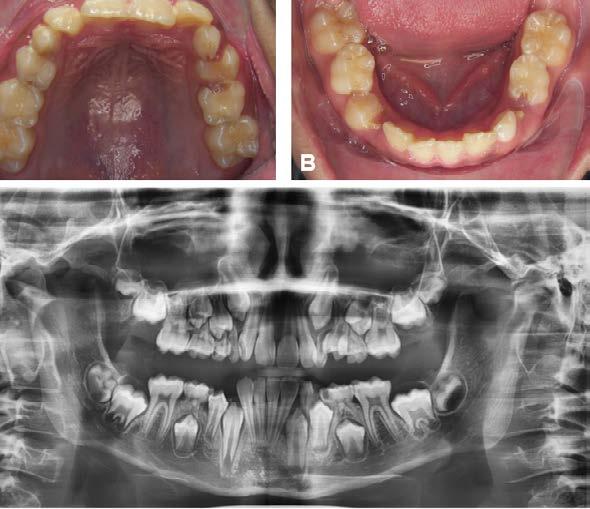

Figura 1. Fotografías intraorales y lateral de cráneo. A. Vista lateral (VL) derecha en oclusión. B. Vista frontal (VF) en oclusión. C. VL izquierda en oclusión. D. Radiografía lateral de cráneo.

Figura 2. Fotografías oclusales y ortopantomografía. A. Vista de la arcada superior. B. Vista de la arcada inferior. C. Ortopantomografía.

Reporte de caso clínico

Paciente masculino de 10 años, se presenta a la consulta en la clínica Gnathos, la mamá reporta desagrado en la estética dental y facial del paciente. En la exploración clínica se observa mordida profunda, amplio número de piezas dentales con caries, fracturas dentales, mala higiene y encías inflamadas. presenta clase II división 2, se le indicaron estudios complementarios para diagnóstico asertivo, modelos de estudio,

Tratamiento de mordida profunda

radiografía panorámica y lateral de cráneo, fotografía intraoral y extraoral, historia clínica y consentimiento informado.